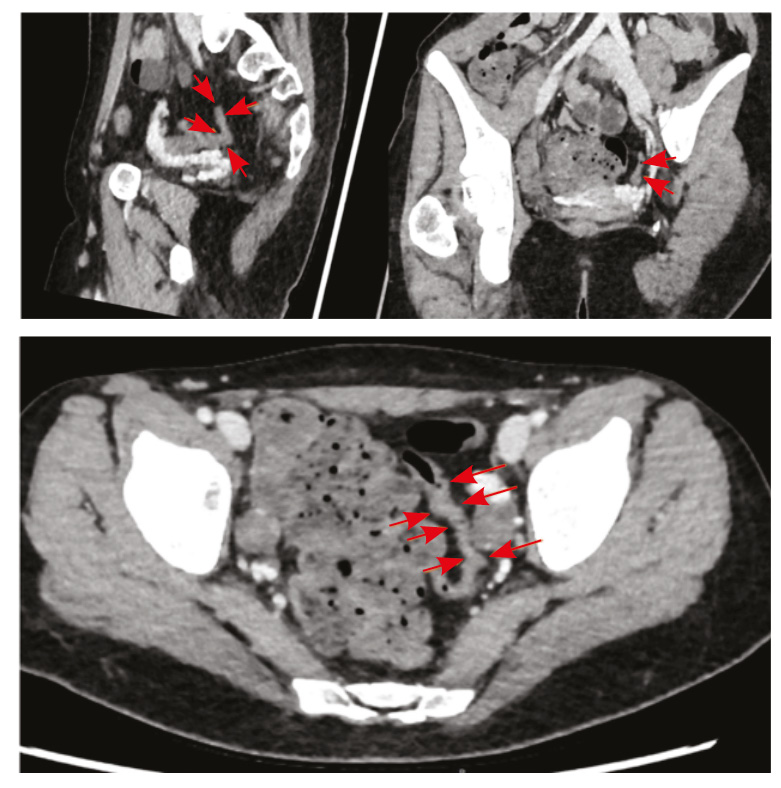

По результатам КТ органов брюшной полости с контрастным усилением, КТ- энтерографии определено утолщение стенки сигмовидной кишки до 5 мм на протяжении 60 мм, стенка без повышенного контрастирования (толщина стенки в остальных отделах не превышала нормы (2–3 мм), петли тонкого и отделы толстого кишечника расположены типично, стенки их с равномерным накоплением контрастного вещества, без достоверного наличия дополнительных образований, рельеф слизистой без отека, параколическая клетчатка не уплотнена, брыжеечные лимфатические узлы не увеличены. Заключение: КТ-признаки утолщения стенок сигмовидной кишки (поствоспалительные, постколитические изменения?), узелковая гиперплазия левого надпочечника (рис. 2).

Рис. 2. Компьютерная томографическая энтерография (30.03.2022). Стрелками указан измененный участок сигмовидной кишки: стенка утолщена до 5 мм на протяжении 60 мм, без повышенного контрастирования

У описанной нами пациентки имелись характерные вышеуказанные признаки – метеоризм, неустойчивый стул, значительная потеря массы тела (13 кг) и обратимая колопатия. При этом изменения стенки кишки локализовались преимущественно в сигмовидной кишке (утолщение стенки сигмовидной кишки на протяжении 60 мм по данным КТ-энтерографии). Сегментарность в данном случае в сочетании со стенозом нижней брыжеечной артерии говорит об ишемическом характере поражения. По данным литературы, поражение брыжеечной артерии при АТ происходит в 11–28% случаев [34] и проявляется дискомфортом в животе, вздутием [35].